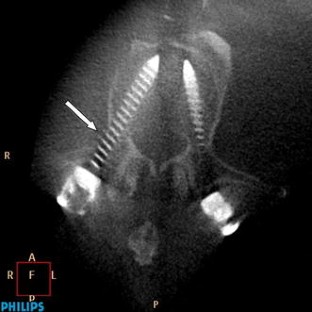

Computer tomography assessment of pedicle screw placement in lumbar and sacral spine: comparison between free-hand and O-arm based navigation techniques

Transpedicular screw fixation has been accepted worldwide since Harrington et al. first placed pedicle screws through the isthmus. In vivo and in vitro studies indicated that pedicle screw insertion accuracy could be significantly improved with image-assisted systems compared with conventional approaches. The O-arm is a new generation intraoperative imaging system designed without compromise to address the needs of a modern OR like no other system currently available. The aim of our study was to check the accuracy of O-arm based and S7-navigated pedicle screw implants in comparison to free-hand technique described by Roy-Camille at the lumbar and sacral spine using CT scans. The material of this study was divided into two groups, free-hand group (group I) (30 patients; 152 screws) and O-arm group (37 patients; 187 screws). The patients were operated upon from January to September 2009. Screw implantation was performed during PLIF or TLIF mainly for spondylolisthesis, osteochondritis and post-laminectomy syndrome. The accuracy rate in our work was 94.1% in the free-hand group compared to 99% in the O-arm navigated group. Thus it was concluded that free-hand technique will only be safe and accurate when it is in the hands of an experienced surgeon and the accuracy of screw placement with O-arm can reach 100%.